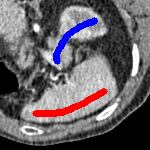

[\capbeside\thisfloatsetupcapbesideposition=left,top,capbesidewidth=1.5in]figure[\FBwidth]

for and as defined in (33). This is consistent with respect to the intensities of the observed object and the concept of selective segmentation. In Fig. 3 we see the difference between CV and the proposed fitting terms for given user input on a CT image. For the CT image, the CV fitting terms are near 0 within the target region. This is despite there being a distinct homogeneous area with good contrast on the boundary. This illustrates the problem we are aiming to overcome. With the proposed fitting term this phenomenon should be avoided in cases like this. By defining as in (33) there is no contradiction if the foreground and background intensities of the target region are similar.